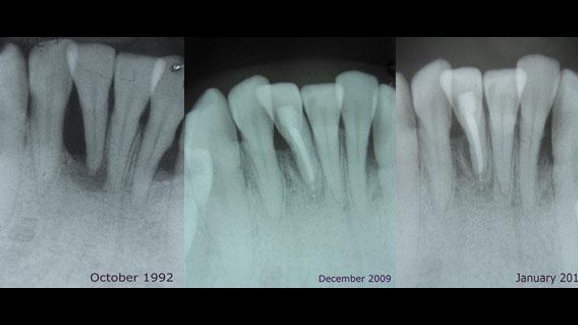

Suite à ce qui semblait être un échec du traitement radiculaire de la dent 26, basé sur un diagnostic clinique et radiologique ...